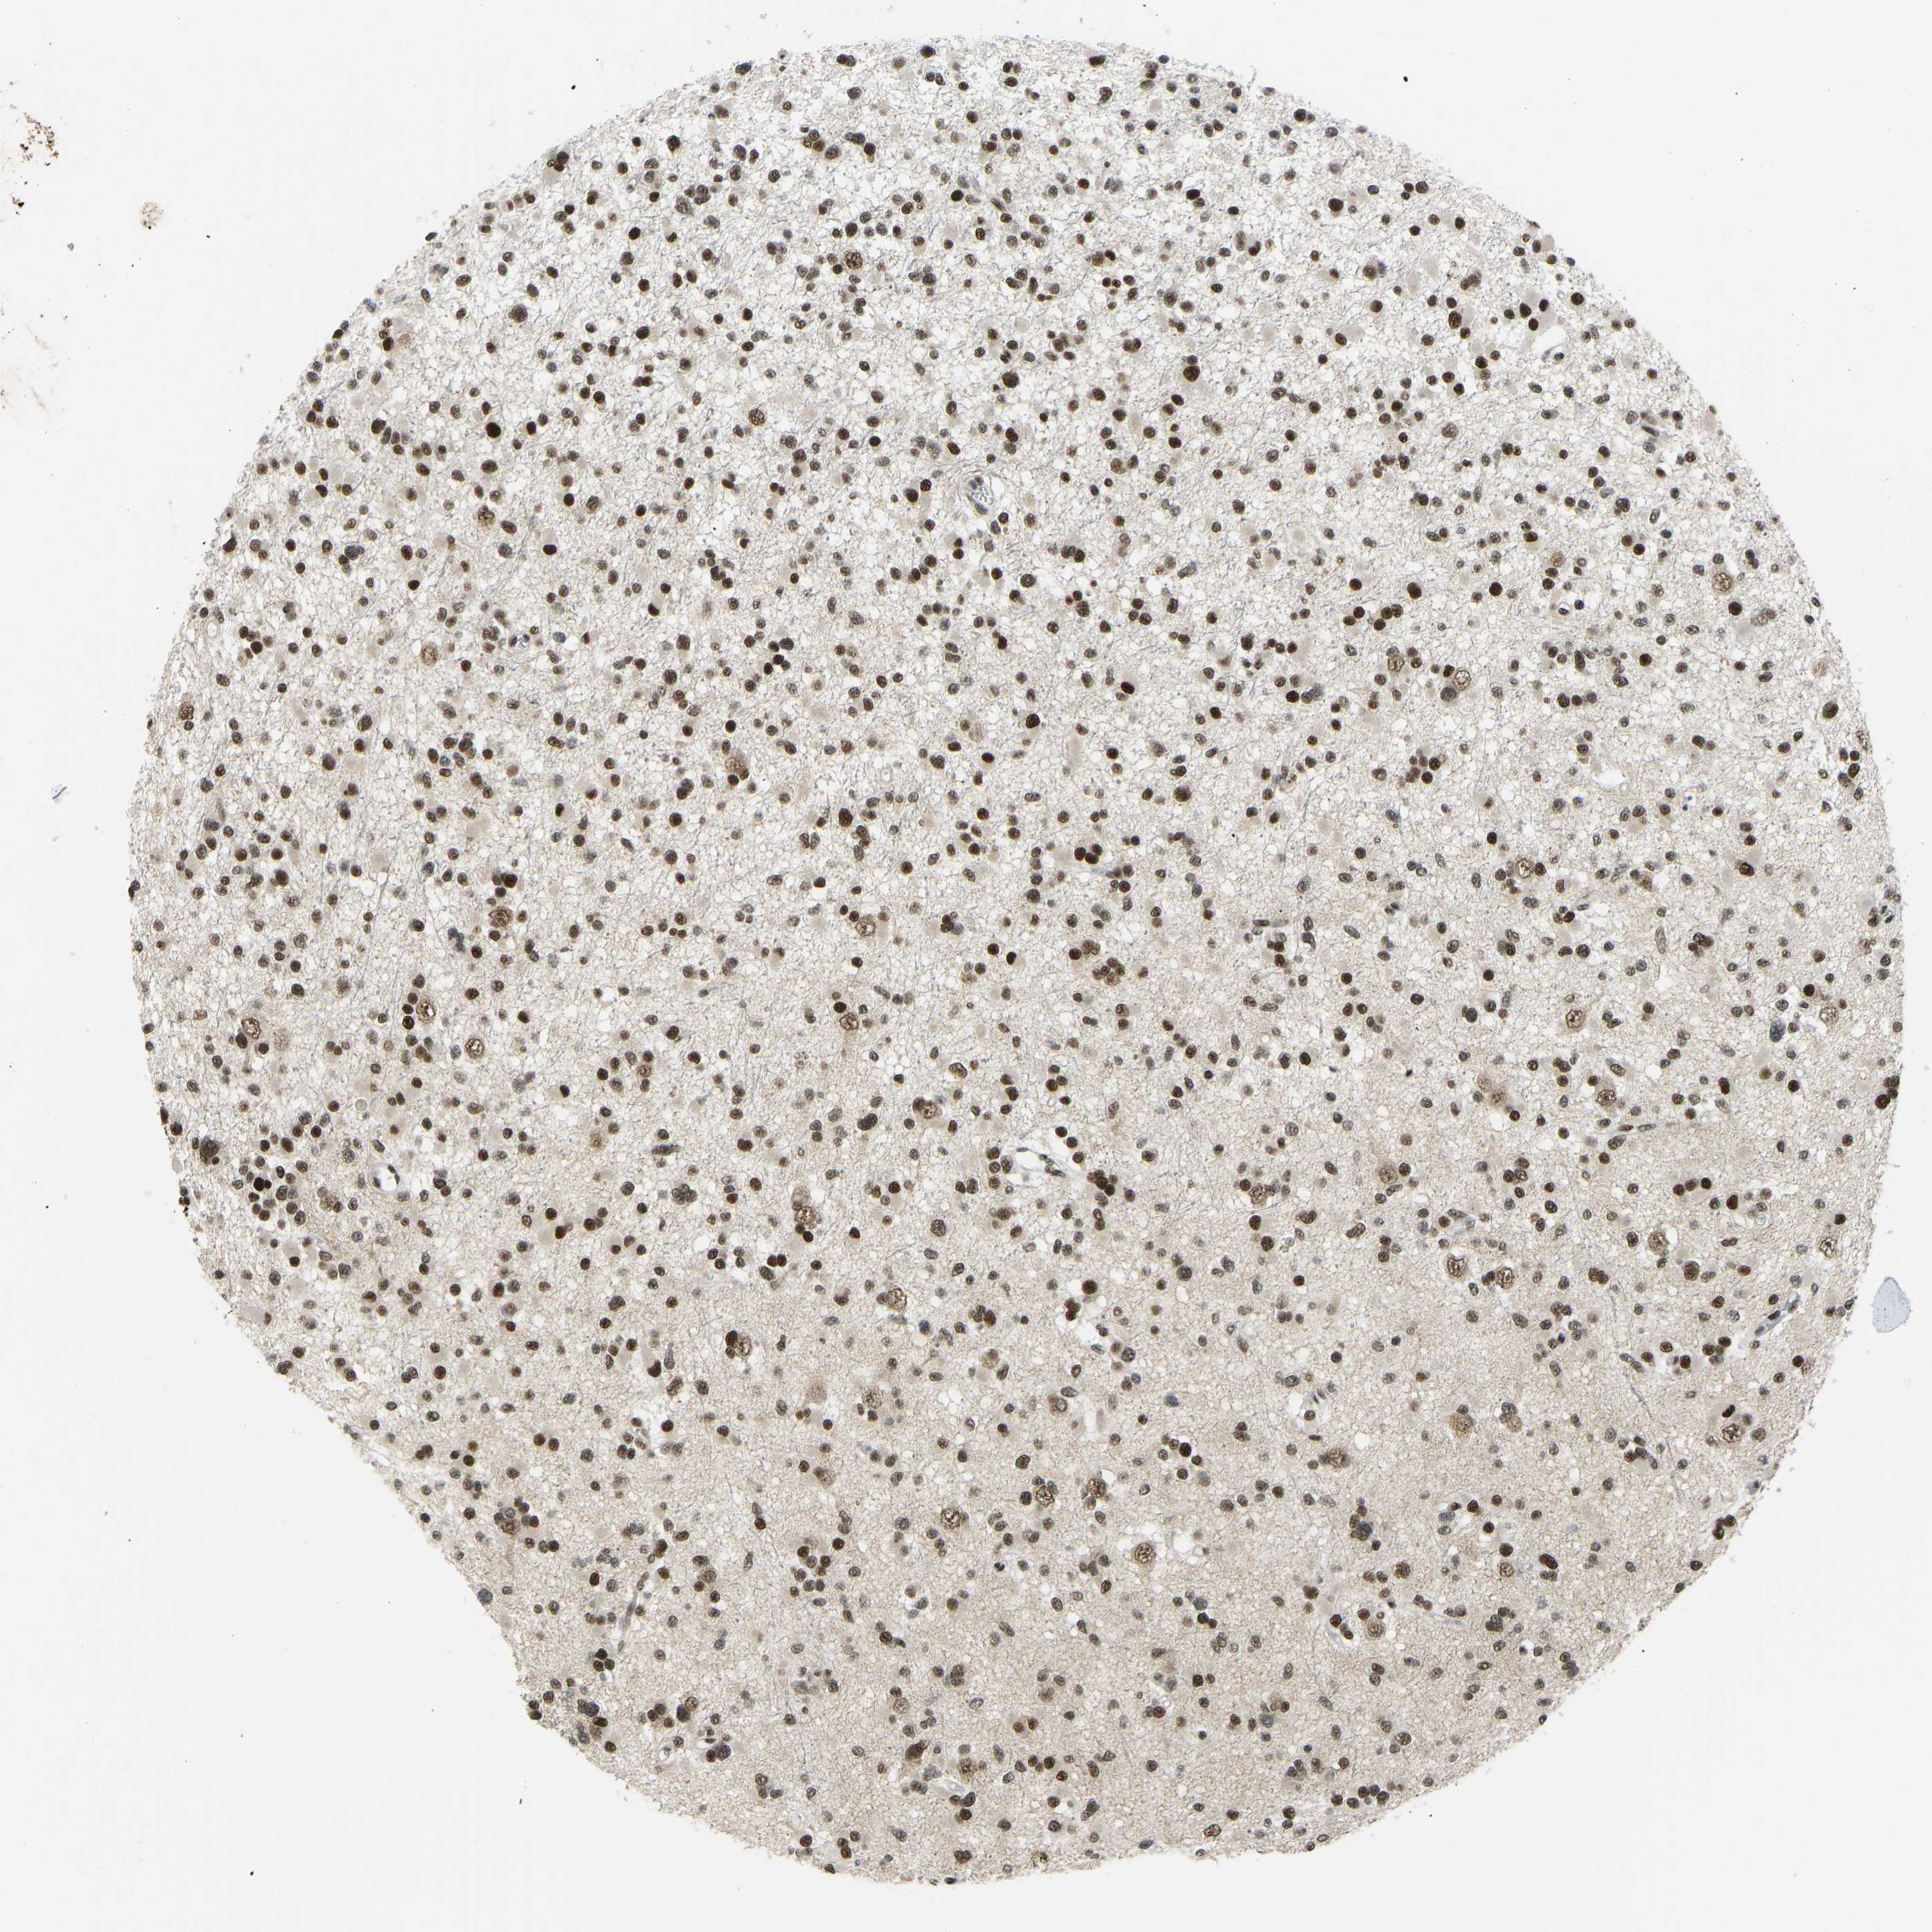

GLIOMA - Protein expressioni

A mouse-over function shows sample information and annotation data. Click on an image to view it in a full screen mode. Samples can be filtered based on level of antibody staining by selecting one or several of the following categories: high, medium, low and not detected. The assay and annotation is described here.

Note that samples used for immunohistochemistry by the Human Protein Atlas do not correspond to samples in the TCGA dataset.

Antibody stainingi

Antibody staining in the annotated cell types in the current human tissue is reported as not detected, low, medium, or high, based on conventional immunohistochemistry profiling in selected tissues. This score is based on the combination of the staining intensity and fraction of stained cells.

Each image is clickable and will lead to virtual microscopy that enables deeper exploration of all samples and also displays staining intensity scores, fraction scores and subcellular localization as well as patient and tissue information for each sample.

Antibody HPA017998

Antibody HPA018864

Staining

High

Medium

Low

Not detected

Intensity

Strong

Moderate

Weak

Negative

Quantity

>75%

75%-25%

<25%

None

Location

Nuclear

Cytoplasmic/membranous

Cytoplasmic/membranous,nuclear

Glioma, malignant, High grade

Glioma, malignant, Low grade